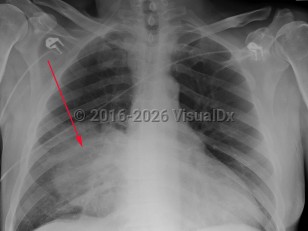

Streptococcus pneumoniae pneumonia

Pneumococcal pneumonia often starts as a single shaking chill. Fevers, cough with sputum, fatigue, and chest pain are common symptoms. Fever may be absent in elderly patients. Examination may reveal crackles on the affected side and signs of consolidation, like dullness to percussion and tubular breath sounds. Also present may be signs of a pleural effusion. Any new heart murmur should raise the suspicion for endocarditis. Otitis media, sinusitis, meningitis, and endocarditis are the other manifestations of pneumococcal infection.